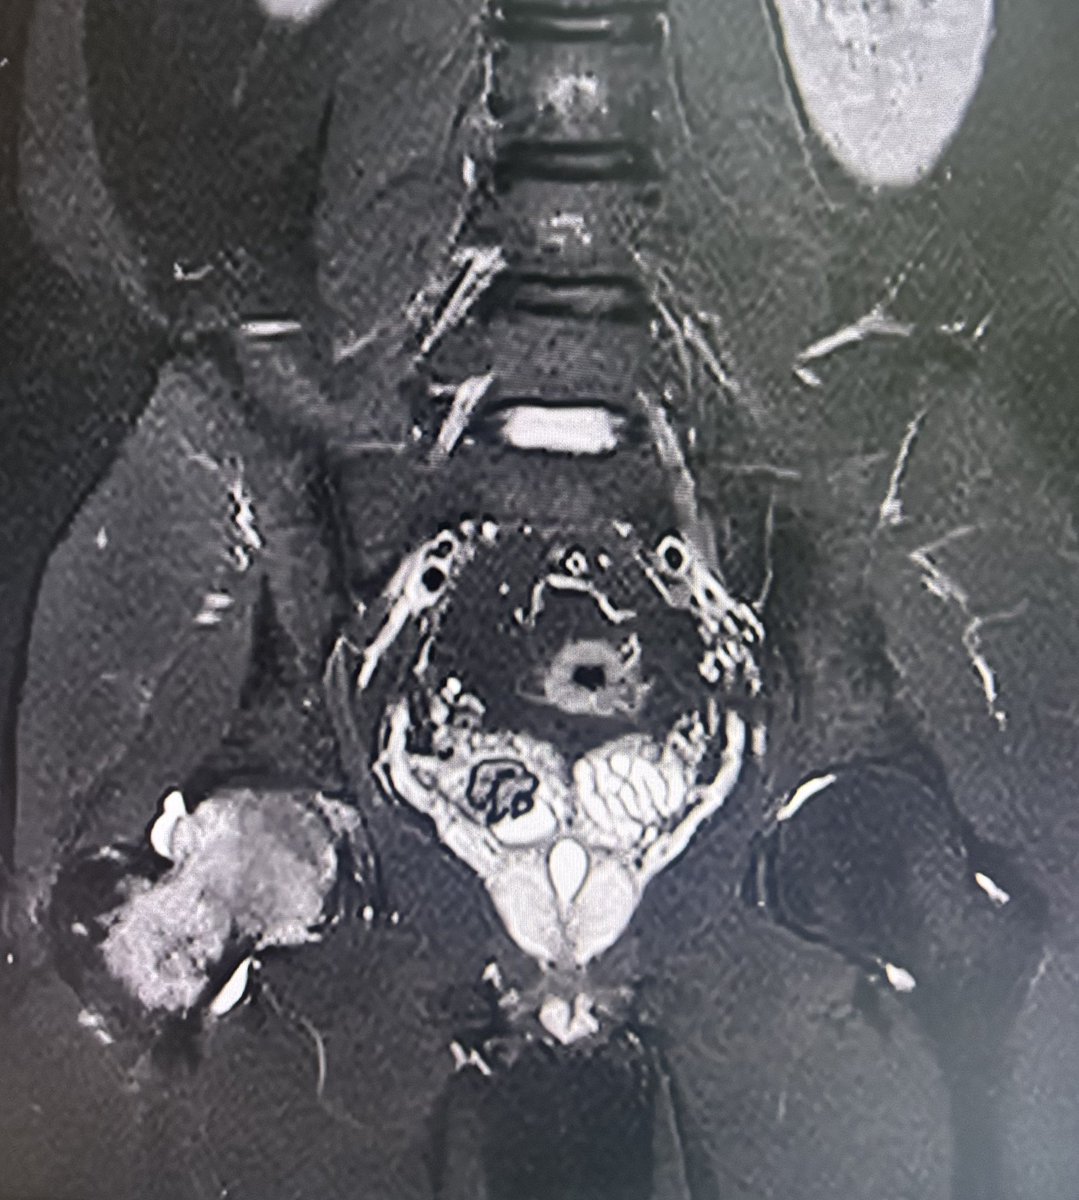

36 year old male with hip pain since 20 days.

What is the most likely diagnosis?

#Orthotwitter

#MSKradiology